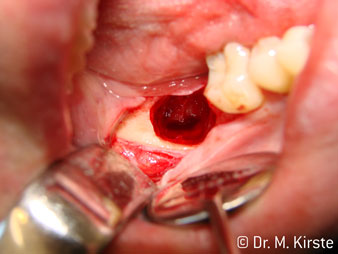

45° açılı angldruva geniş avantaj yelpazesi sebebiyle özellikle seçildi. Bu enstrümanın geliştirilme nedeni olan cerrah meslektaşlarım angldruvaların kısıtlı alanlardaki çalışma yeteneğini yakında takdir edeceklerdir. Özellikle gömük diş çekimlerinde (res. 2) yumuşak dokunun yanak bölgesine doğru yarılmasına gerek kalmaz(res. 3). Angldruvanın kafa dizaynı sayesinde retromolar bölgede hızlı ve güvenli çalışma sağlar.

Angldruva kafası içindeki profesyonel tasarımlı dişliler frezin sessiz çalışmasını garanti eder; kök separasyonu yapılırken atravmatik operasyona olanak verir. (res. 4-9).